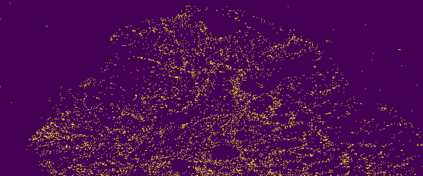

The usage of chemical imaging technologies is becoming a routine accompaniment to traditional methods in pathology. Significant technological advances have developed these next generation techniques to provide rich, spatially resolved, multidimensional chemical images. The rise of digital pathology has significantly enhanced the synergy of these imaging modalities with optical microscopy and immunohistochemistry, enhancing our understanding of the biological mechanisms and progression of diseases. Techniques such as imaging mass cytometry provide labelled multidimensional (multiplex) images of specific components used in conjunction with digital pathology techniques. These powerful techniques generate a wealth of high dimensional data that create significant challenges in data analysis. Unsupervised methods such as clustering are an attractive way to analyse these data, however, they require the selection of parameters such as the number of clusters. Here we propose a methodology to estimate the number of clusters in an automatic data-driven manner using a deep sparse autoencoder to embed the data into a lower dimensional space. We compute the density of regions in the embedded space, the majority of which are empty, enabling the high density regions to be detected as outliers and provide an estimate for the number of clusters. This framework provides a fully unsupervised and data-driven method to analyse multidimensional data. In this work we demonstrate our method using 45 multiplex imaging mass cytometry datasets. Moreover, our model is trained using only one of the datasets and the learned embedding is applied to the remaining 44 images providing an efficient process for data analysis. Finally, we demonstrate the high computational efficiency of our method which is two orders of magnitude faster than estimating via computing the sum squared distances as a function of cluster number.